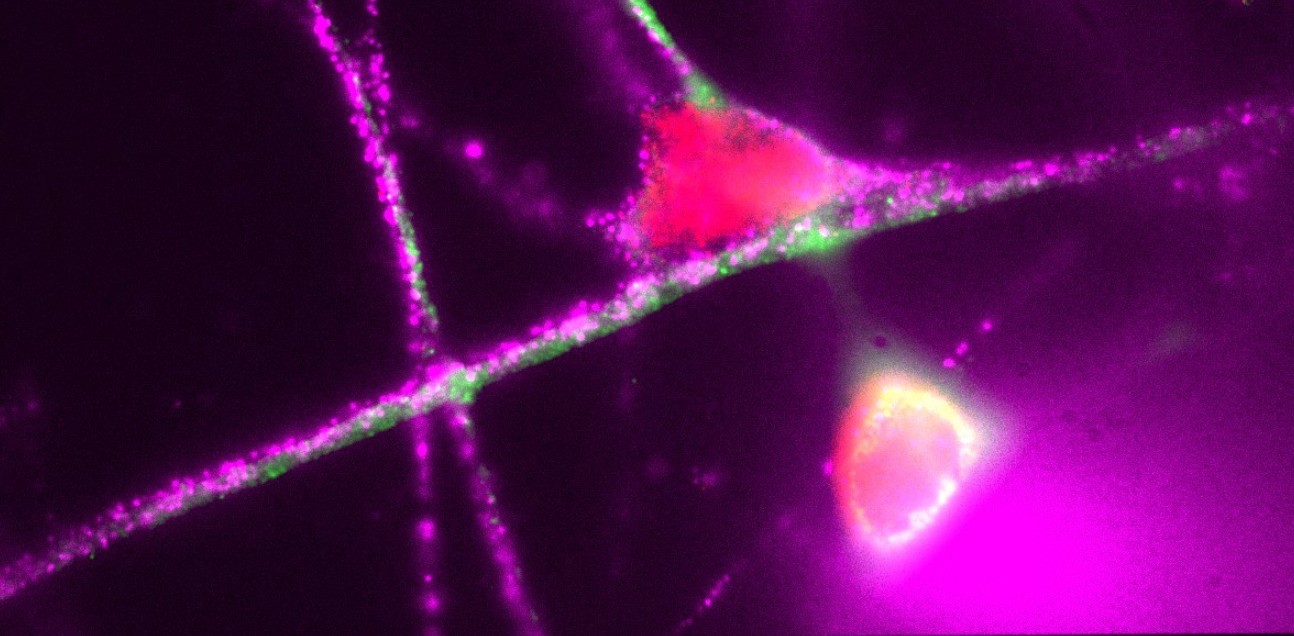

iPSC Derived Neuron - Emma Mee-Hayes (Research Associate: Ye lab)

"iPSC Derived Neuron. Stained for MAP2 (green), LMP7 (pink) and PSMB2 (red)."